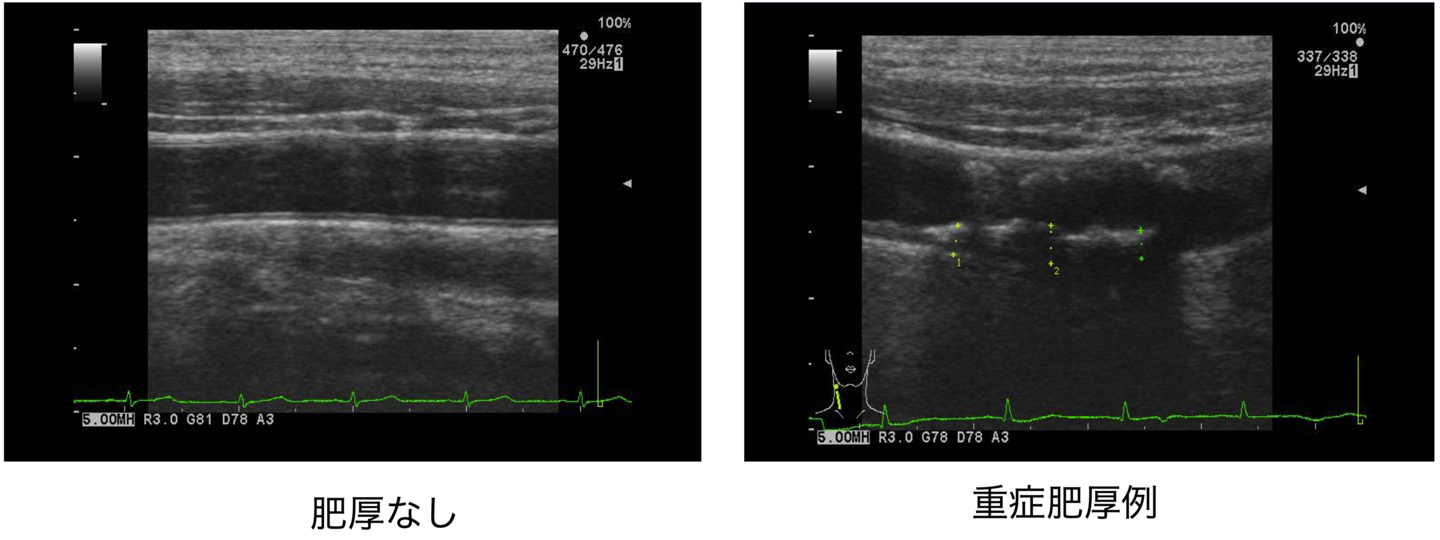

- アキレス腱肥厚はX線撮影により男性 8mm以上、女性7.5mm以上、あるいは、超音波により男性6mm以上、女性5.5mm以上にて診断する。

アキレス腱肥厚の診察

エコー検査(初診時および1年に1回)